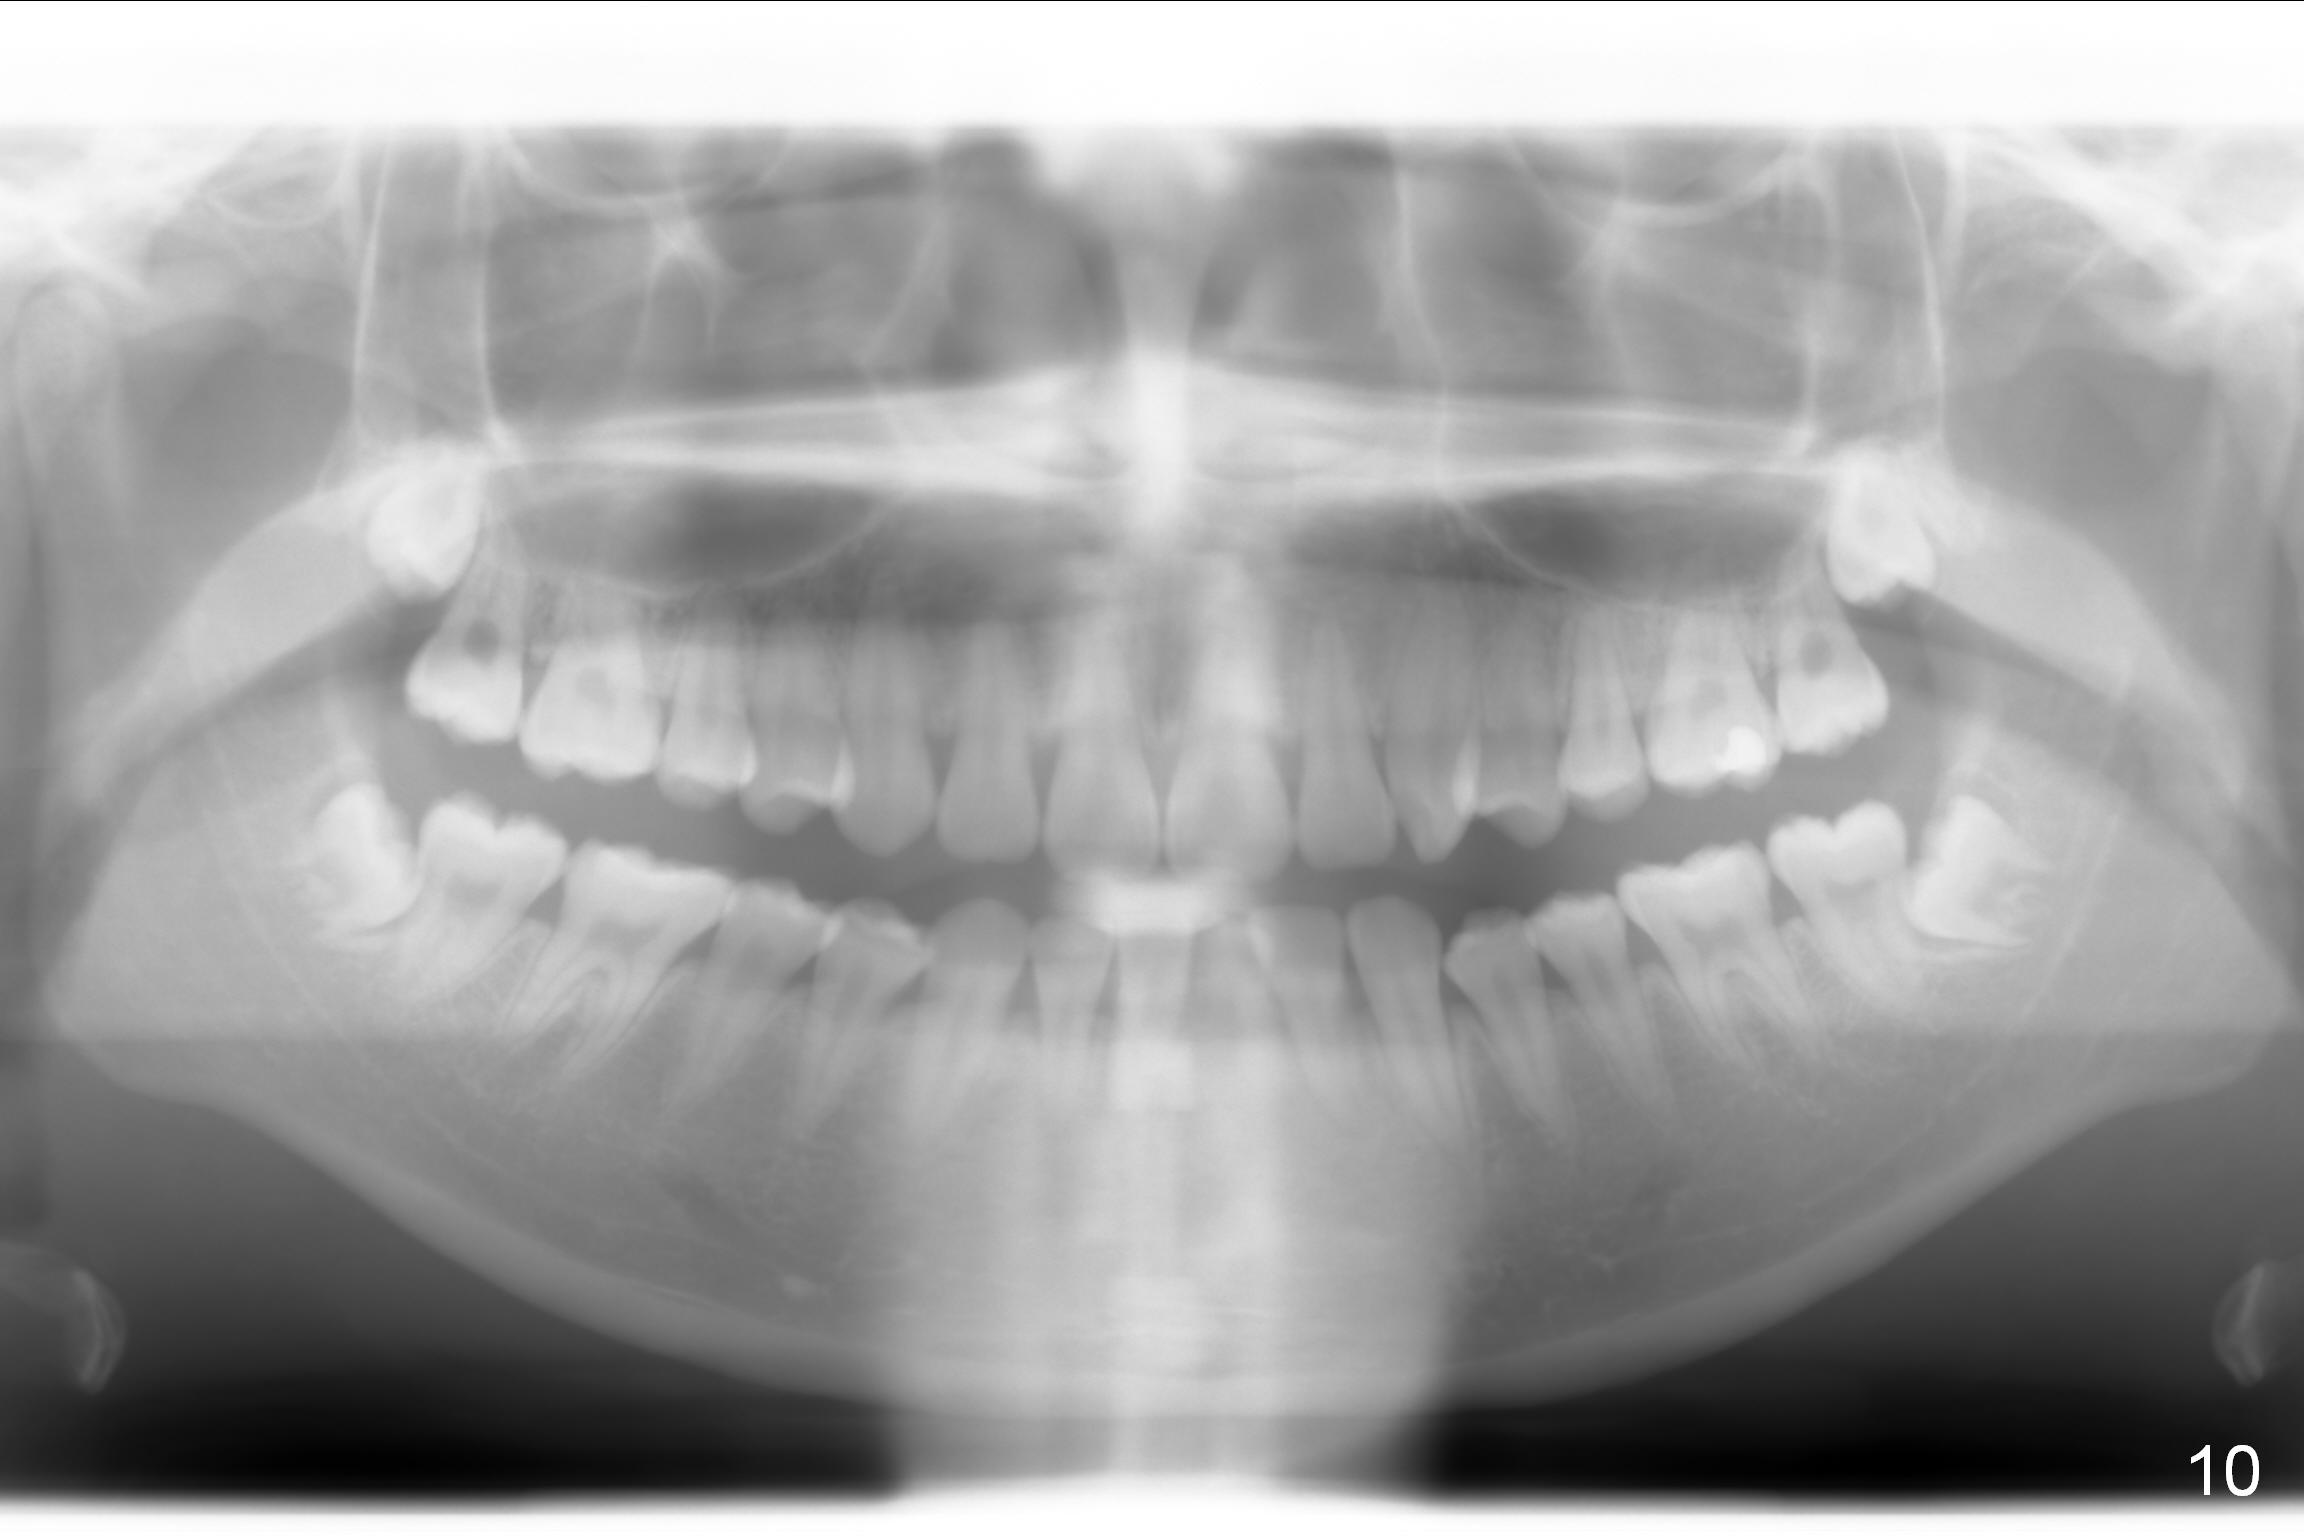

The goal of orthodontic treatment is to achieve normal anterior over bite and over jet and canine and molar Class I occlusion. When we take photos for these patients, we need to consider the facial proportion (frontal and profile views should include the forehead, Fig.1-6), facial and dental midlines (Fig.2, 8) and posterior occlusion.

To show the posterior occlusion directly, use the smaller single cheek retractor to retract the corner of the mouth as posterior as possible. For better exposure, ask the patient to hold a mouth mirror lightly at the other corner of the mouth. The camera should be also positioned posteriorly with focus on the region between the canine (mainly) and the 1st molar (as compared to Fig.7 and 9).

Jessica is a 15-year-old Chinese. She cares about her upper central incisors and the upper left canine (rotation). Place rotation wedges as early as possible and overcorrect the rotation.

Do you like her profile (Fig.3,6)? Are the lips a little protrusive? According to Caucasian standard, the normal lips should be behind the imaginary line from the middle of the nasal base to the chin (Fig.4 white line). Jessica's lips appear to be protrusive. The ideal treatment would be 4 bicuspid extraction.

When the imaginary line is drawn from the tip of the nose and the chin, her lips are just behind it (Fig.5). It appears that her lip position is not so bad. Take the same profile photos in the late stage of orthodontic treatment and re-analyze the lip position. Proximal reduction will be performed if the lips are protrusive. If the upper lip is too protrusive, use Class II retraction with elastics.